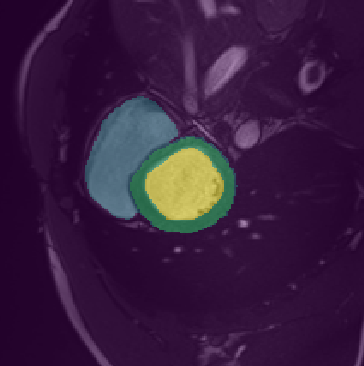

In this paper, we aim to improve the performance of semantic image segmentation in a semi-supervised setting in which training is effectuated with a reduced set of annotated images and additional non-annotated images. We present a method based on an ensemble of deep segmentation models. Each model is trained on a subset of the annotated data, and uses the non-annotated images to exchange information with the other models, similar to co-training. Even if each model learns on the same non-annotated images, diversity is preserved with the use of adversarial samples. Our results show that this ability to simultaneously train models, which exchange knowledge while preserving diversity, leads to state-of-the-art results on two challenging medical image datasets.